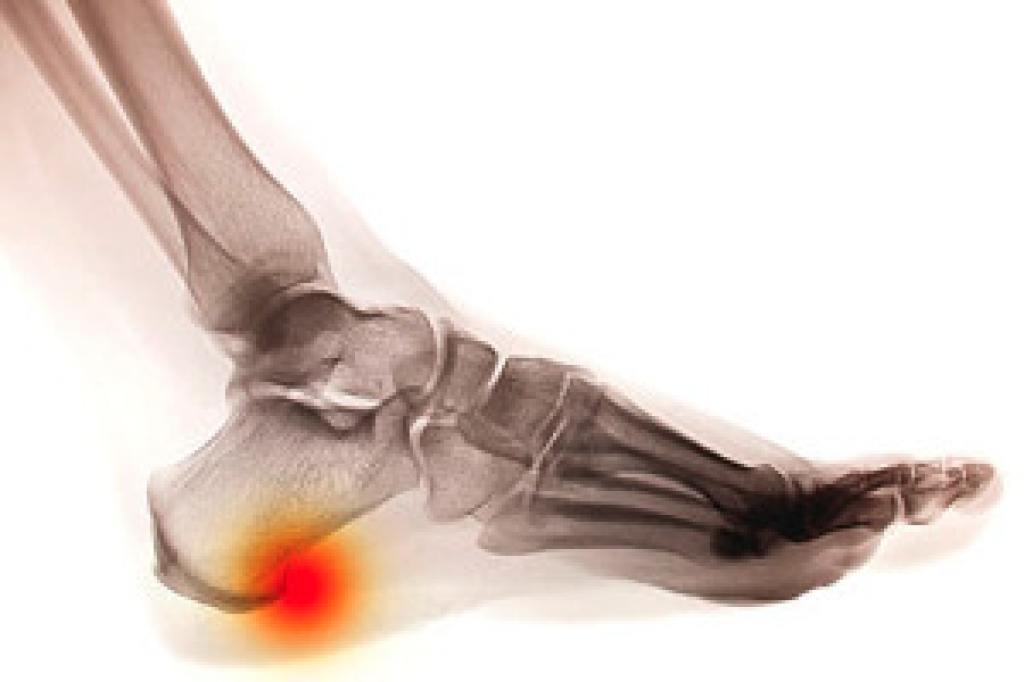

The Achilles tendon is one of the longest tendons in the body, and its purpose is to connect the heel bone to the calf. If an injury should occur to the Achilles tendon, severe pain may be felt. An acute tear to the Achilles tendon is often due to a sports mishap. If you are involved in tennis, soccer, volleyball, or similar sports, this type of injury may be more likely to occur. If you feel that damage may have been done to the Achilles tendon, swelling, stiffness, and reduced strength in the foot may be experienced. To determine the severity of the injury, an MRI or ultrasound may be performed. Treatment will typically consist of resting the foot, wearing different footwear, or using orthotic devices. Schedule a consultation with your podiatrist for a proper evaluation if you believe you've sustained an Achilles tendon injury.

The Achilles tendon is a tendon that connects the lower leg muscles and calf to the heel of the foot. It is the strongest tendon in the human body and is essential for making movement possible. Because this tendon is such an integral part of the body, any injuries to it can create immense difficulties and should immediately be presented to a doctor.

There are various types of injuries that can affect the Achilles tendon. The two most common injuries are Achilles tendinitis and ruptures of the tendon.

Achilles tendon injuries are diagnosed by a thorough physical evaluation, which can include an MRI. Treatment involves rest, physical therapy, and in some cases, surgery. However, various preventative measures can be taken to avoid these injuries, such as: